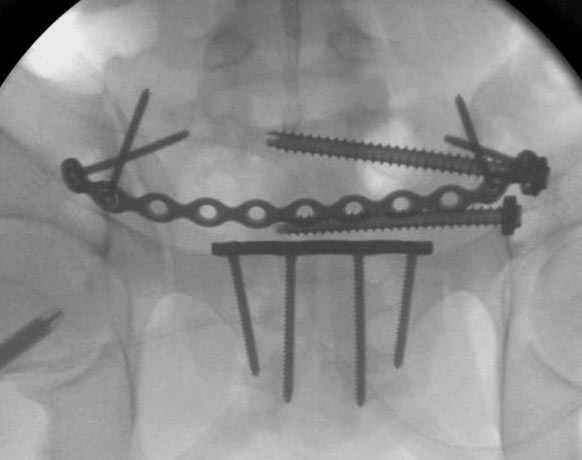

Здесь слайды случая больного с политравмой, включающей сегментарный перелом бедра и повреждение таза с нарушением тазового кольца, разрыв симфиза и перелома крестца зон 2 и 3.

На множественных слайдах важные моменты операции. Хотел бы подчеркнуть, как важно иметь возможности всех необходимых ренгенограмм, включая компютерную томографию и стандартных внутритазовых рентгенограмм (инлет и оутлет).

Djoldas Kuldjanov, MD

Department of Orthopedic Surgery

St. Louis University Medical Center